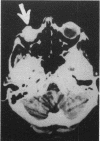

A blind painful eye may harbour an unsuspected malignant melanoma. We report a case of ocular melanoma that presented with confusion owing to direct extension via the optic nerve into the anterior cranial fossa.